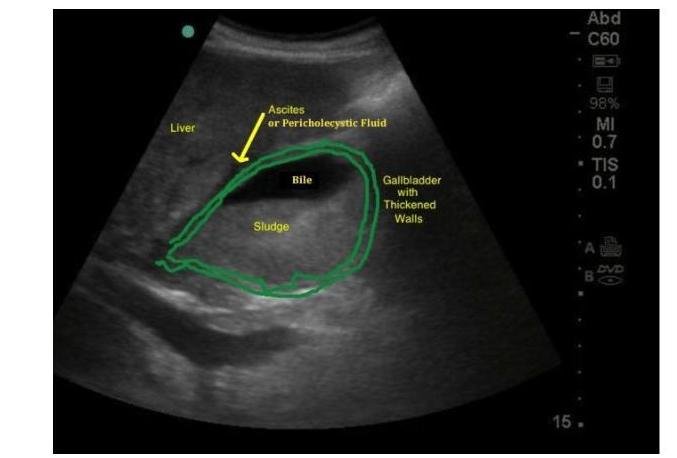

# COLELITIASIS Y COLECISTITIS ## DEFINICIÓN ## COLECISTITIS Es la inflamación de la vesícula biliar ocasionada principalmente por **cálculos (litos)** y con menor frecuencia por **barro (lodo) biliar**, aunque en raras ocasiones ninguna de estas dos está presente. ## COLELITIASIS O litiasis biliar, es la presencia de cálculos dentro de la vesícula biliar. Habitualmente, los cálculos biliares se forman en la vesícula biliar, pero pueden hacerlo a cualquier nivel del tracto biliar. ## COMPOSICIÓN Habitualmente están formados por una mezcla de colesterol, bilirrubinato cálcico, proteínas y mucina. 1. Colesterol (80%) 2. Pigmentarios (común en asiáticos) a. Negros: Bilirrubina, Carbonato, Fosfato, Calcio b. Marrones: Bilirrubinato cálcico, Ac. Palmítico 3. Mixta (la más común) ## ANATOMÍA  ## CHOLECYSTITIS Cystic Duct Gallbladder Gallstones Duodenum Minor Duodenal Papilla  # EPIDEMIOLOGÍA - La colecistitis aguda es una de las principales causas de consulta en el servicio de urgencias y en la consulta externa de cirugía general. - La **colecistitis** se presenta en el 5-20 % de los pacientes con **colelitiasis**. - La colecistitis aguda se presenta con mayor frecuencia en **mayores de 40 años**. - Femenino 2: 1 Masculino. - La colecistectomía es el procedimiento más común realizado por los cirujanos generales. - Los adultos producen entre 500-1,000 ml de Bilis al día. ## FACTORES DE RIESGO | FACTORES DE RIESGO LITOS DE COLESTEROL | FACTORES DE RIESGO LITOS PIGMENTADOS (Bilirrubina con Sales de Calcio o Bilirrubinato) | | :--: | :--: | | - Dislipidemias - **Muy importante** - Female (**mujeres**) - Forty (**mayores a 40 años**) - Fat (**Obesidad**) - Fertility (**Embarazo**) - Fármacos (**fibratos** y la **ceftriaxona**) - Anticonceptivos Orales y Terapia con Estrógenos - Enfermedades del íleon - Enfermedades Hepáticas y Metabólicas (Cirrosis, Diabetes Mellitus) - Antecedentes Familiares de Litiasis Biliar | - Trastornos hemolíticos - Cirrosis - Edad avanzada - Ser Asiático | - Las mujeres tienen el doble de riesgo con respecto a los hombres de presentar colecistitis y colelitiasis. - En cuanto a cirugías realizadas, la relación es Mujer 4 : 1 Hombre. - En el embarazo es frecuente la formación de cálculos de colesterol, normalmente son formas asintomáticas de litiasis biliar y tanto el barro biliar como los cálculos menos de 10 mm desaparecen tras el parto. - Los anticonceptivos orales y la terapia hormonal sustitutiva con estrógenos, en este caso con mayor riesgo en mujeres menores de 40 años y las que reciben una dosis mayor de 50 microgramos de estrógenos. # CLÍNICA Las manifestaciones clínicas de colecistitis y colelitiasis son las siguientes: ## COLELITIASIS Y COLECISTITIS AGUDA NO COMPLICADA 1. Signo de Murphy positivo 2. Masa en cuadrante superior derecho 3. Dolor en cuadrante superior derecho 4. Resistencia muscular en cuadrante superior derecho 5. Náusea y vómito ## COLELITIASIS Y COLECISTITIS COMPLICADA - Vesícula palpable - Fiebre mayor de 39^{\circ} C - Calosfríos - Inestabilidad Hemodinámica ## COLELITIASIS Y COLECISTITIS + PERFORACIÓN DE VESÍCULA CON PERITONITIS Se debe sospechar con los siguientes datos: | - Aumento dolor forma súbita | - Taquipnea | | :-- | :-- | | - Signos de irritación peritoneal difusa | - Acidosis Metabólica | | - Distensión abdominal | - Hipotensión | | - Taquicardia | - Choque. | ## CLASIFICACIÓN | GRADO I - LEVE | Colecistitis aguda en paciente saludable y sin disfunción orgánica. Cambios inflamatorios leves en la vesícula biliar. Colecistectomía segura con bajo riesgo operatorio. | | :--: | :--: | | GRADO II - MODERADA | Colecistitis aguda acompañada de las siguientes condiciones: - Leucocitosis Elevada (>18,000) - Masa palpable en cuadrante superior derecho - Duración del cuadro clínico >72 horas - Inflamación local (peritonitis biliar, absceso perivascular, hepático, enfisema). Requiere Internamiento + Antibióticos IV. | | GRADO III - GRAVE | Colecistitis aguda acompañada por **Daños a órgano o sistema**: - Disfunción cardiovascular (hipotensión que requiere dopamina o dobuta) - Disfunción neurológica (disminución del nivel de conciencia) - Disfunción respiratoria ( PaO2/Fio2 promedio <300) - Disfunción renal (oliguria, Creatinina >2.0 ) - Disfunción hematológica (plaquetas <100,000 ) | # DIAGNÓSTICO Considerar diagnóstico con: Signo o Síntoma Local + Signo Sistémico + Estudio de Imagen positivo. ## LABORATORIO No existen pruebas de laboratorio específicas para colecistitis aguda, sin embargo, las siguientes pueden tener utilidad: - Biometría Hemática: puede aparecer leucocitosis. - Proteína C Reactiva: puede hallarse elevada y es de utilidad para confirmar proceso inflamatorio. - Otras: Bilirrubinas, BUN, Creatinina, Tiempo de Protrombina, Amilasa (para identificar complicaciones como Coledocolitiasis, no confundir con Pancreatitis [se necesita el triple de su valor]). - Hemocultivo/Cultivo: deberá ser solicitado en presencia de fiebre y sospecha de cuadro infeccioso para seleccionar el agente microbiano. ## ESTUDIO DE IMAGEN ## 1ra elección: Ultrasonido - Ante la sospecha de colecistitis o colelitiasis aguda es la prueba no invasiva de primera elección. - El USG abdominal es positivo en el 98 % de los casos (sensibilidad). ## Hallazgos que reporta el USG: - Engrosamiento de la pared vesicular +5 mm - Líquido perivesicular - Signo de Murphy ultrasonográfico positivo - Alargamiento vesicular 8 cm axial y 4 cm diametral - Lito encarcelado - Imagen de doble riel - Sombra acústica posterior (presencia de lito) - Ecos intramurales  ## GAMMAGRAFÍA BILIAR (Escintografía) Tiene sensibilidad del 97 % y se debe solicitar cuando la clínica y la ecografía no fueron concluyentes. ## TOMOGRAFÍA AXIAL COMPUTARIZADA - Engrosamiento de pared vesicular - Colecciones líquidas perivasculares - Alargamiento vesicular - Áreas de alta densidad en el tejido graso perivesicular ## RESONANCIA MAGNÉTICA - Signos de pericolecistitis con imágenes de alta densidad - Alargamiento vesicular - Engrosamiento de pared vesicular # GAMMAGRAFÍA VÍA BILIAR CON TC-HIDA - Exclusión vesicular - Signo de Rim (aumento de la radioactividad alrededor de la fosa vesicular)  ## DIAGNÓSTICO DIFERENCIAL Ante el reporte negativo de las pruebas diagnósticas para la **Colelitiasis y Colecistitis** se deberá realizar el diagnóstico diferencial con alguna de las siguientes entidades: - Úlcera péptica perforada - Apendicitis aguda - Obstrucción intestinal - Pancreatitis aguda - Cólico renal o biliar - Colangitis aguda bacteriana - Pielonefritis - Hepatitis aguda - Hígado congestivo - Angina de pecho - Infarto de miocardio - Rotura de aneurisma aórtico - Tumores o abscesos hepáticos - Herpes zoster - Síndrome de Fitz-Hugh-Curtis # TRATAMIENTO ## FARMACOLÓGICO Estará reservado para los pacientes en situaciones especiales por alto riesgo quirúrgico o que rechazan cirugía. ## 1ra elección: Ácido Ursodesoxicólico / Ácido Quenodeoxicólico - Para la disolución de los cálculos biliares el tratamiento de elección son los ácidos biliares orales. - Debe emplearse por un periodo de 1-2 años. - También se usa como coadyuvante cuando se realiza litotricia, mayor efectividad de destrucción. ## AINES ## 1ra elección: Diclofenaco 75 mg IM - En pacientes con cólico biliar es recomendable para prevenir aparición de colecistitis aguda. - Si ya existe colecistitis aguda, no demuestran remisión de la enfermedad. ## OPIOIDES - En presencia de dolor intenso se puede manejar con Meperidina. ## ANTIBIÓTICO La elección dependerá de la susceptibilidad local por el antibiograma, la administración previa de un antibiótico, de la disfunción renal o hepática y de la gravedad de la colecistitis. (Guías Sanford). | Colecistitis Grado I | 1ra elección: Un solo antibiótico A. Fluoroquinolonas Orales (Levofloxacino o Ciprofloxacino) B. Cefalosporinas Orales (Cefotiam, Cefcapene) C. Penicilinas Amplio Espectro (Ampicilina con Sulbactam) | | :--: | :--: | | Colecistitis Grado II | 1ra elección: Doble Antibiótico A. Penicilinas de Amplio Espectro (Pipe/Tazo o Ampicilina con Sulbactam) B. Cefalosporinas de segunda generación (Cefmetazole, Cefotiam, Oxacefem, Flomoxef) | | Colecistitis Grado III | 1ra elección: Doble antibiótico más potente. A. Cefalosporinas de 3ra y 4ta generación (Ceftriaxona, Ceftazidima, Cefepime, Cefozopran, Cefoperazona con Sulbactam) B. Monobactámicos (Aztreonam) Metronidazol cuando se detecta o se sospecha de anaerobios (casos complicados). | MICROORGANISMOS: La bilis es estéril; una intervención, manipulación o estasis de ella aumenta la probabilidad de contaminación: **E. coli, Klebsiella, Enterobacter** (**Gram negativos**). # LITOTRICIA La litotricia + disolutos orales (Sales biliares) no ofrecen suficiente evidencia para ser indicado como tratamiento en presencia de litiasis vesicular y no está aprobado por la FDA como tratamiento definitivo, pero la GPC recomienda realizarla en las siguientes situaciones: ## Indicaciones para litotricia - Pacientes con **litiasis única**. - **No** calcificada. - Diámetro de 20-30 mm. ## Contraindicaciones para litotricia - Pancreatitis - Alteraciones de la coagulación - Quistes o aneurismas en el trayecto de las ondas ## QUIRÚRGICO ## 1ra elección: Colecistectomía Esta puede ser realizada por laparotomía o laparoscopía. | Colecistectomía Temprana | Se realiza 1 - 7 días después del ataque inicial. | | :--: | :--: | | Colecistectomía Tardía | Se realiza 2 - 3 meses después del ataque inicial. | ## COLECISTECTOMÍA LAPAROSCÓPICA Se prefiere a la abierta por: menor mortalidad, menores complicaciones, menor estancia hospitalaria, reincorporación laboral rápida. ## FACTORES QUE DIFICULTAN CIRUGÍA LAPAROSCÓPICA: - Masculinos - Cirugía abdominal previa - Presencia o antecedentes de Ictericia - Colecistitis en fase avanzada - Infecciones graves | COMPLICACIONES LAPAROSCÓPICA | - Lesión del conducto biliar - Lesión del intestino - Lesión hepática - Infección de sitio quirúrgico | | :--: | :--: | | COMPLICACIONES ABIERTA | - Infecciones - Íleo - Hemorragia intraperitoneal - Atelectasia - Trombosis de venas profundas - Infección del tracto urinario | ELECCIÓN DE LA TÉCNICA QUIRÚRGICA | GRADO I - LEVE | 1ra elección: Colecistectomía Temprana por Laparoscopía. | | :--: | :--: | | GRADO II - MODERADA | 1ra elección: Colecistectomía Temprana por Laparoscopía, sin embargo, depende de la experiencia del cirujano para el abordaje. Si presenta inflamación grave de la vesícula se recomienda un drenaje temprano que puede ser quirúrgico o percutáneo. Si se hay inflamación grave de la vesícula la colecistectomía temprana puede ser difícil, se recomienda posponer cirugía hasta que disminuya la inflamación. | | GRADO III - GRAVE | 1ra elección: Colecistectomía Laparoscópica, sin embargo, dependerá del cirujano y su pericia instrumental. - Manejo urgente de la falla orgánica - Tratamiento de inflamación local - Drenaje de vesícula - Se realiza cirugía cuando las condiciones generales mejoren. | # CPRE La combinación de extracción de litos por endoscopía durante una colangio - pancreatografía retrógrada endoscópica y la colecistectomía laparoscópica es de utilidad en el tratamiento. El intervalo entre estos dos procedimientos es de pocos días, debe hacerse en el mismo tiempo intrahospitalario. ## SEGUIMIENTO - Se deberá realizar por el servicio de cirugía hasta su egreso hospitalario. - Será evaluado una semana después del egreso en la consulta externa de cirugía general. - Se valorará alta de servicio y contrarreferencia a primer nivel. # RECUPERACIÓN ## ESTANCIA HOSPITALARIA | COLECISTECTOMÍA LAPAROSCÓPICA | 1 día de estancia es suficiente. | | :-- | :-- | | COLECISTECTOMÍA ABIERTA NO COMPLICADA | 2-3 días postquirúrgicos. | ## INCAPACIDAD | TÉCNICA | TIEMPO MÍNIMO | ÓPTIMO | MÁXIMO | | :-- | :--: | :--: | :--: | | LAPAROSCÓPICA | 10 | 14 | **21** | | LAPAROSCÓPICA NO COMPLICADA | 14 | 21 | **28** | | ABIERTA | 14 | 21 | **28** | | ABIERTA COMPLICADA | 21 | 28 | **45** | # ALGORITMO ABORDAJE